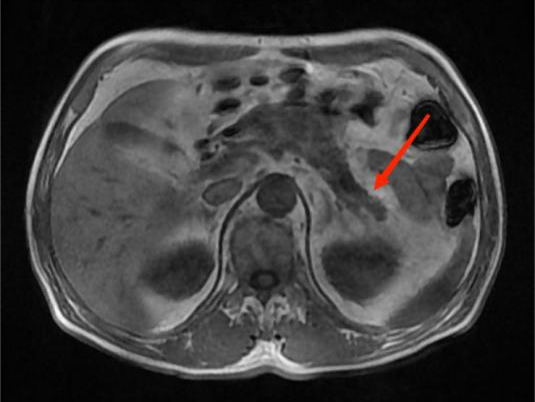

图4A

图4B

图4C

图4D

典型病例4:

男性,59岁,间断左中上腹部疼痛2个月,为隐痛,程度较轻,伴夜间痛。图A:T1WI示胰腺体部见团片状稍低信号影,边界不清。图B:增强扫描示病灶呈弱强化。图C:胰腺体尾部实质萎缩。图D:MRCP示远端胰管扩张。